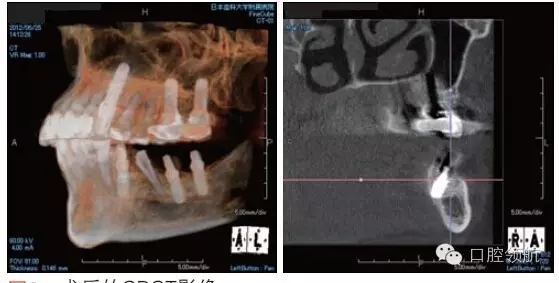

利用曲面斷層及CBCT檢查埋入部位情況,雖未出現與主訴相關的神經損傷,但無意中卻發(fā)現了種植體的舌側穿孔(圖1、圖2)。

圖2 術后的CBCT影像。